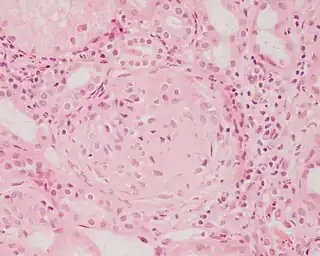

Imagen histopatológica de una muestra de glomerulonefritis con semilunas obtenida de un paciente con glomerulonefritis rápidamente progresiva positiva para anticuerpos anti-MPO-ANCA. Tinción con hematoxilina y eosina.

En la biopsia de estos pacientes se halla una importante proliferación de las células epiteliales de la cápsula de Bowman, con formación de semilunas en los glomérulos.[4] La biopsia renal confirma la presencia de una glomerulonefritis con semilunas epiteliales. Entre las características histopatológicas figura la infiltración del espacio urinario por células mononucleares asociada con la proliferación del epitelio parietal de la cápsula de Bowman o la proliferación extracapilar con formación de semilunas que pueden afectar del treinta al cien por ciento de los glomérulos. En estos se ve un engrosamiento de la cápsula de Bowman con formación de semilunas. También puede haber fibrosis parcial y sinequia del penacho glomerular a la cápsula.[4] Las semilunas, que pueden ser segmentarias o circunferenciales, ocupan todo el espacio de Bowman y ahogan el ovillo capilar, según el estado evolutivo pueden clasificarse en celulares, fibrocelulares o fibrosas y representan fases progresivas del mismo proceso.[4] En la glomerulonefritis rápidamente progresiva de tipo I hay positividad lineal sobre todo para IgG pero después también para C3. Dos tercios de las glomerulonefritis semilunares de este tipo corresponden al síndrome de Goodpasture y el otro tercio carece de manifestaciones pulmonares (síndrome de Goodpasture sin compromiso pulmonar). La lesión glomerular es similar en ambos grupos y se produce por un mecanismo inmunitario antimembrana basal glomerular. Como ya se dijo, el factor desencadenante es un defecto de un componente proteico de la cadena α3 del colágeno de tipo IV.[5] En la enfermedad de tipo II hay positividad granular o nodular o de ambas formas, difusa y global, debido a depósitos de complejos inmunes que con el microscopio electrónico se ven como depósitos densos. Este tipo por lo general corresponde a variedades de la glomerulonefritis aguda difusa, de la glomerulonefritis mesangiocapilar y, menos a menudo, de la enfermedad de Berger.[5]